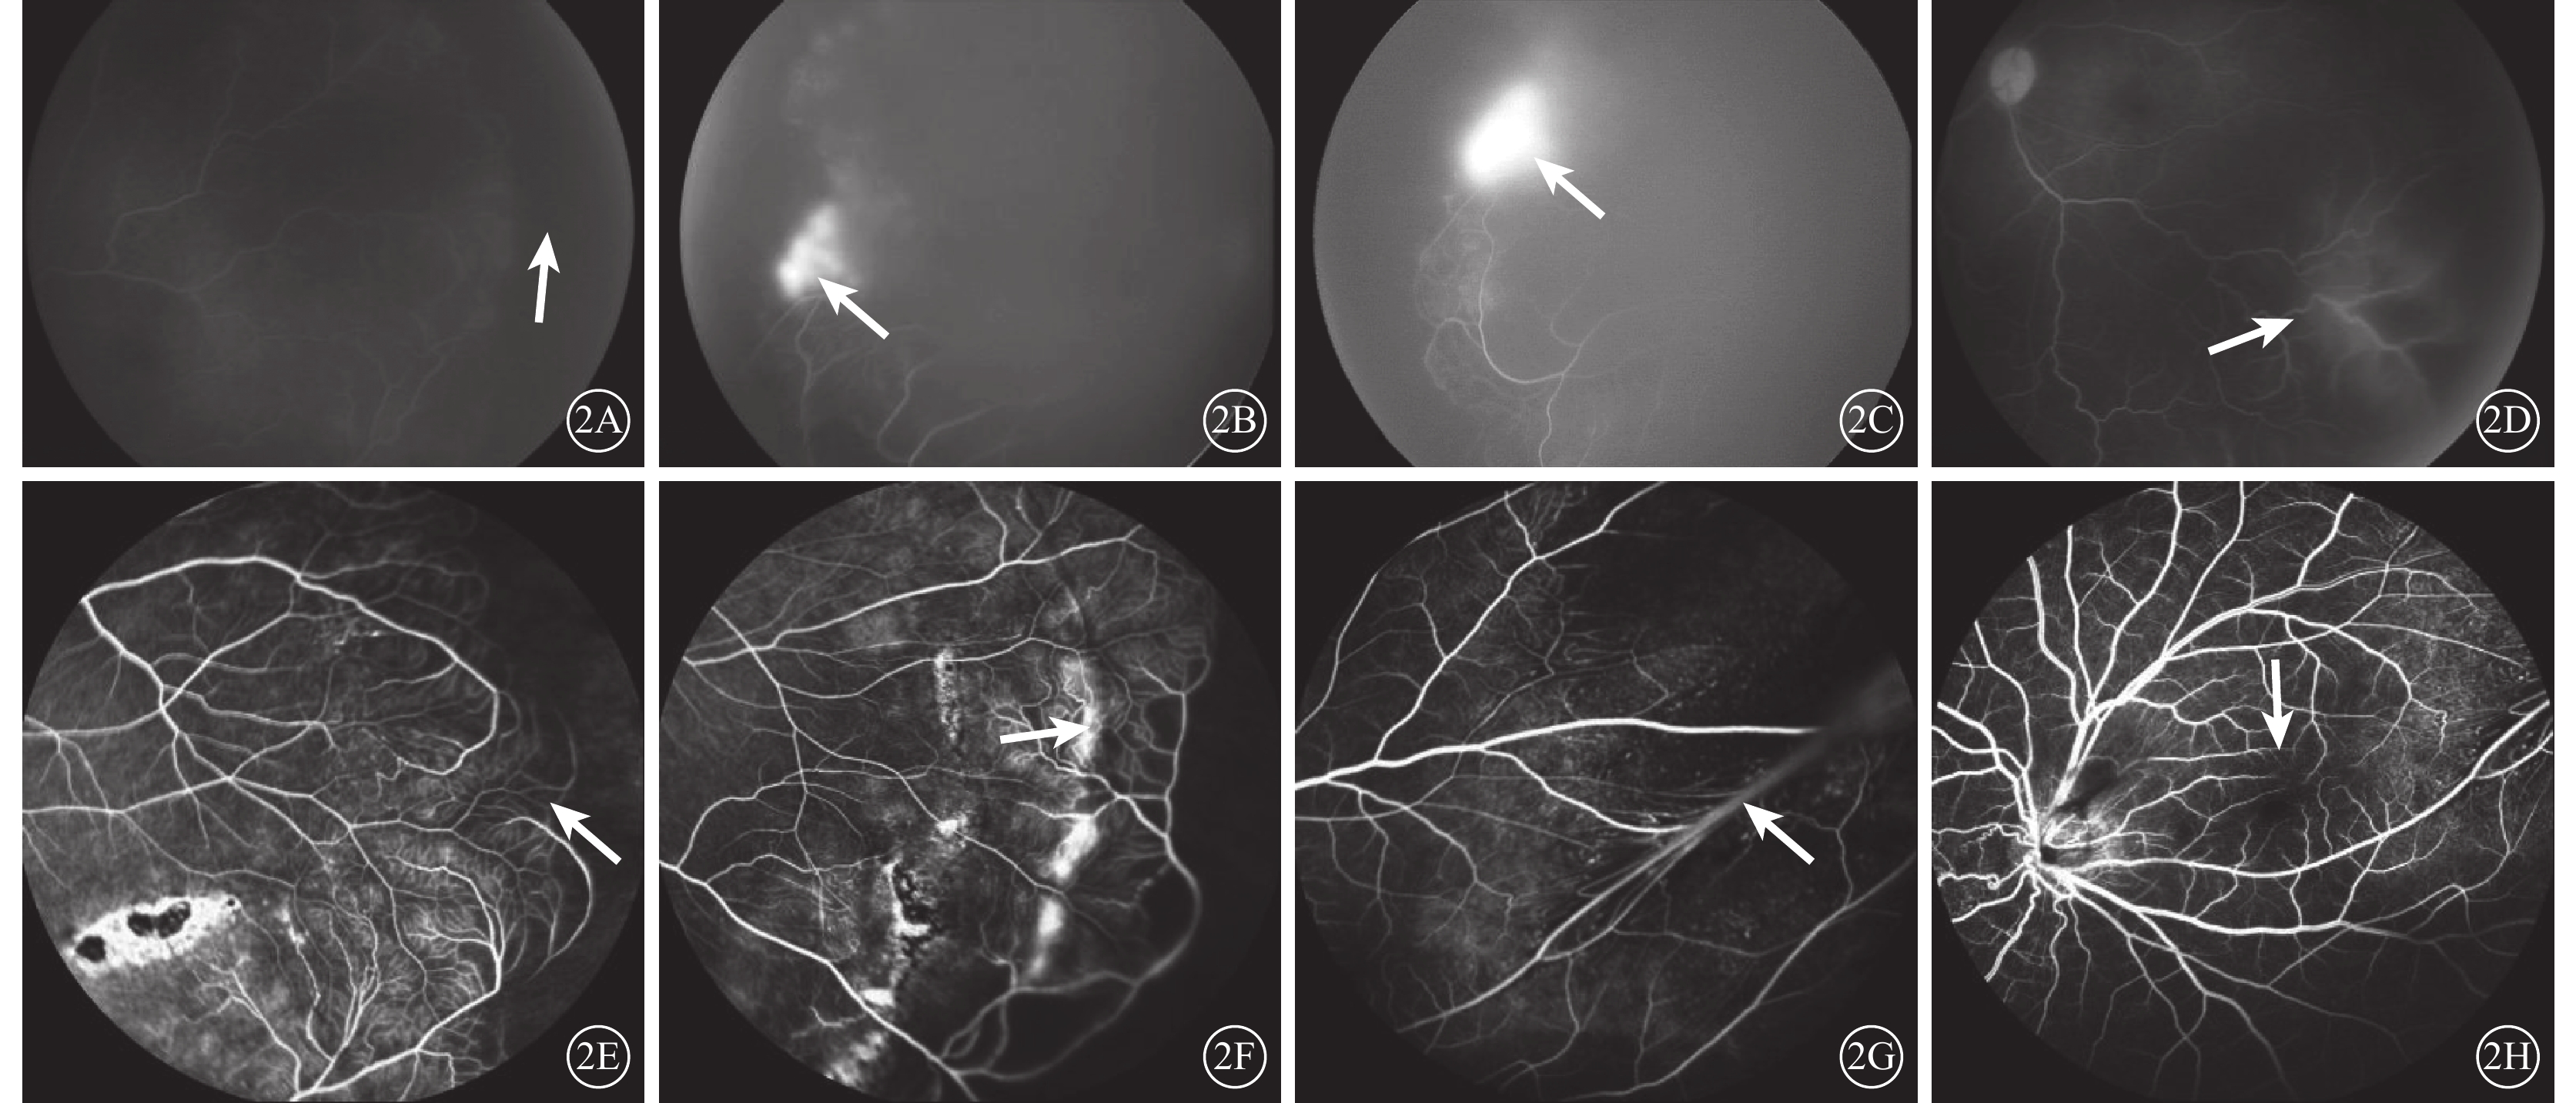

11例15只眼行FFA檢查,7例7只眼因對側眼全視網膜脫離未行FFA檢查。其中,未見明顯異常1只眼,視網膜周邊無血管區(圖2A)13只眼(86.7%,13/15),視網膜新生血管局灶性強熒光且晚期熒光素滲漏增大(圖2B)6只眼(40%,6/15),視網膜末梢血管紆曲、擴張伴輕微熒光素滲漏者(圖2C)9只眼(60%,9/15),視網膜周邊部血管吻合支(圖2D)6只眼(40%,6/15),周邊末梢血管襻樣改變(圖2E)4只眼(26.7%,4/15),視網膜皺襞(圖2F)2只眼(13.3%,2/15),黃斑區無血管區縮小(圖2G)2只眼(13.3%,2/15),黃斑部異常視網膜血管1只眼(6.7%,1/15),視網膜前出血1只眼(6.7%,1/15)。